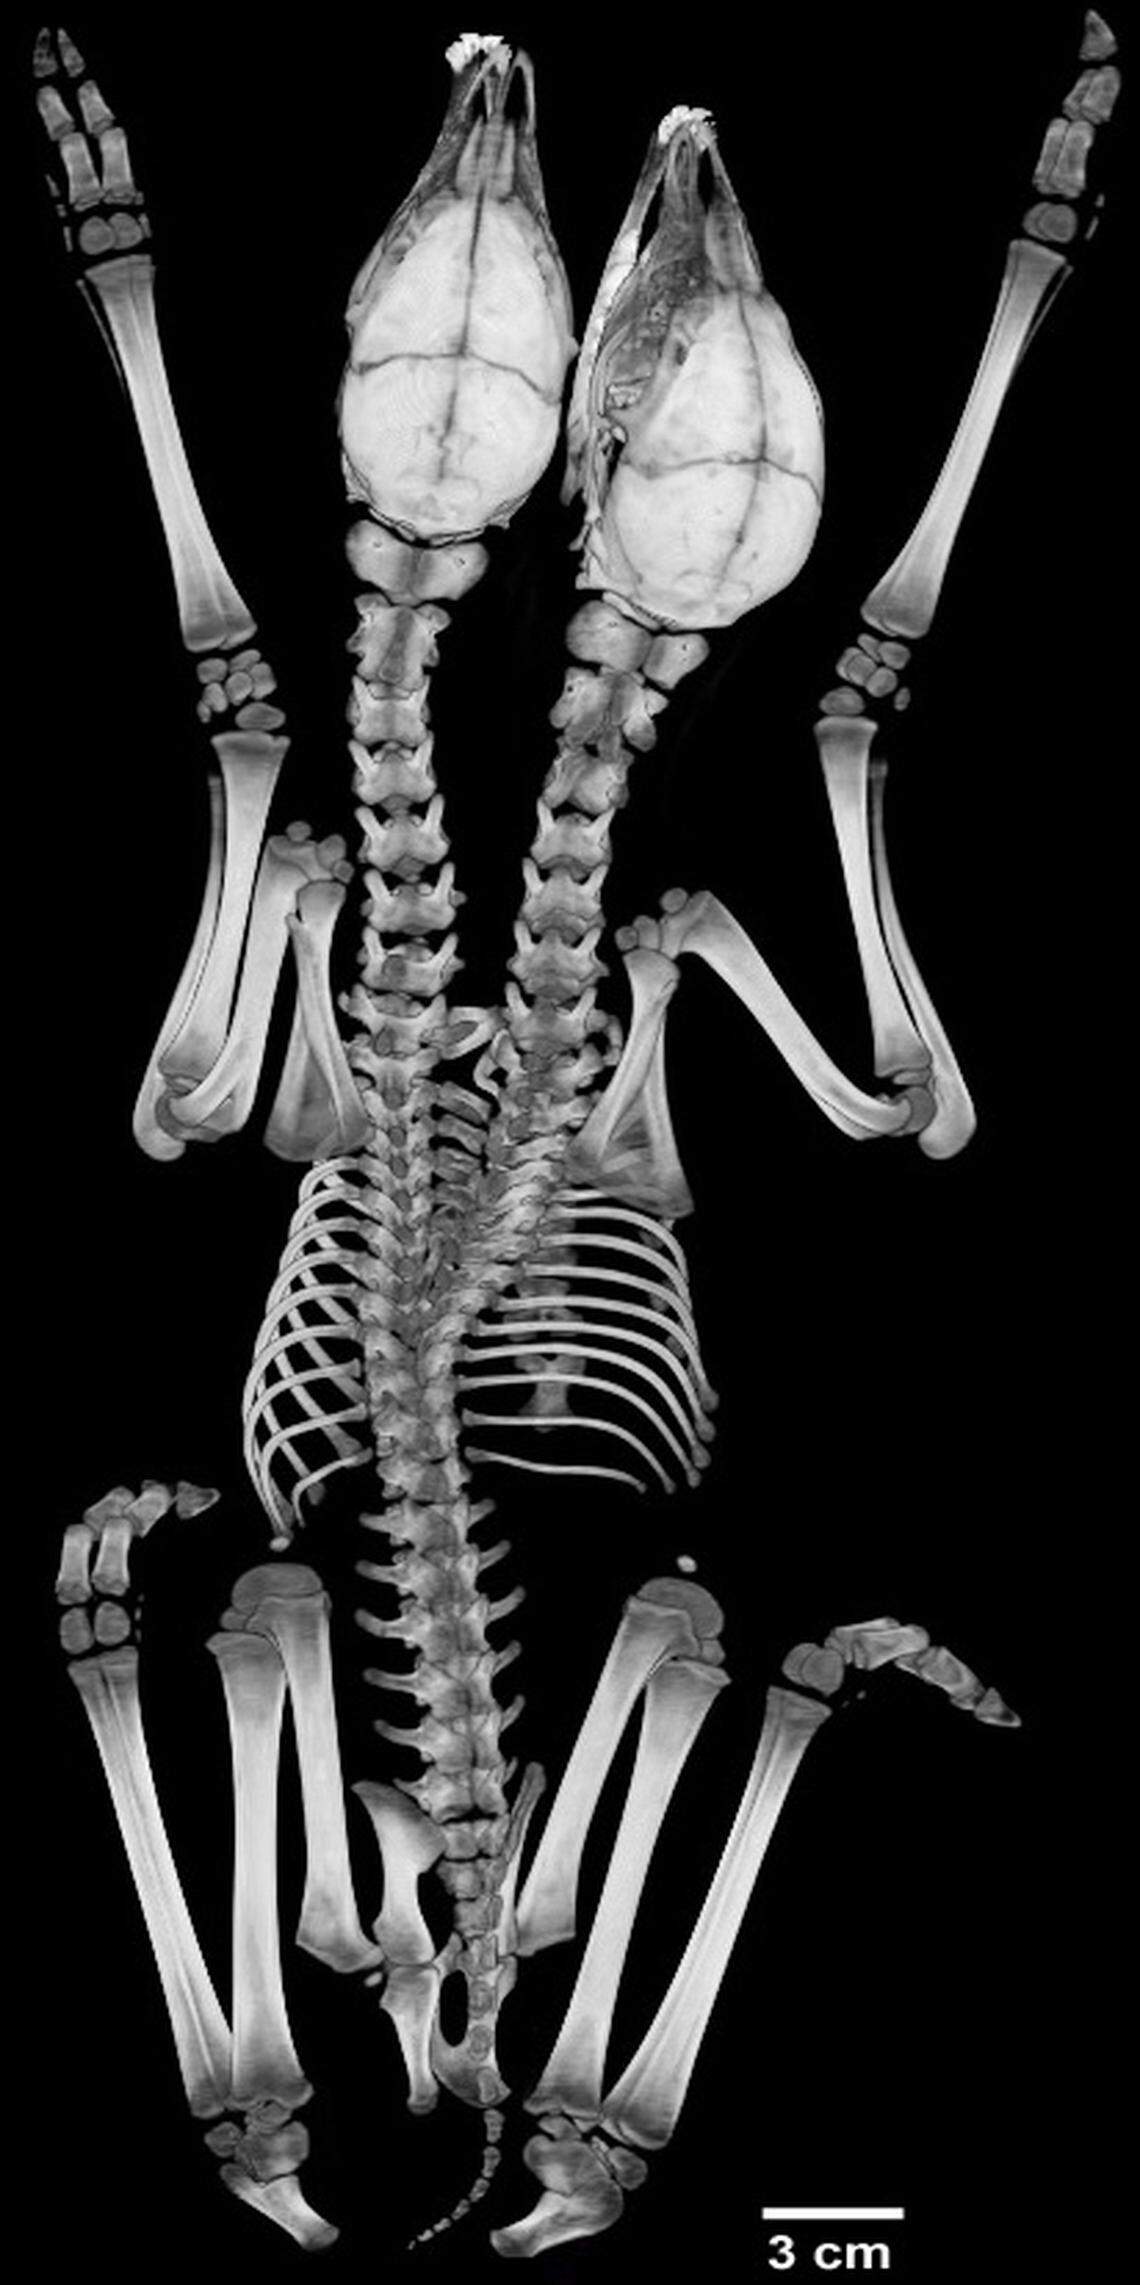

Separate heads and necks are visible in a CT scan of the conjoined fawns.

Separate heads and necks are visible in a CT scan of the conjoined fawns. University of Georgia

After that, scientists ran a battery of tests: a full necropsy, a CT scan and magnetic resonance imaging at the University of Minnesota Veterinary Diagnostic Laboratory, researchers said. And now D’Angelo and other researchers have published a paper describing the rare deformity. It appears in the April edition of the journal American Midland Naturalist.

The fawns had never breathed outside air, tests on their lungs revealed. That confirmed that the twins were stillborn. The necropsy showed that the pair shared a liver, which was malformed, and that they had extra intestinal tracts and spleens, researchers said. As for their hearts, there were two — but with one shared pericardial sac, which is the fibrous tissue that surrounds the heart.

The Minnesota Department of Natural Resources will have the fawns on display — in stuffed form — at their headquarters in St. Paul. The University of Minnesota Veterinary Anatomy Museum will have a skeletal display, researchers said.